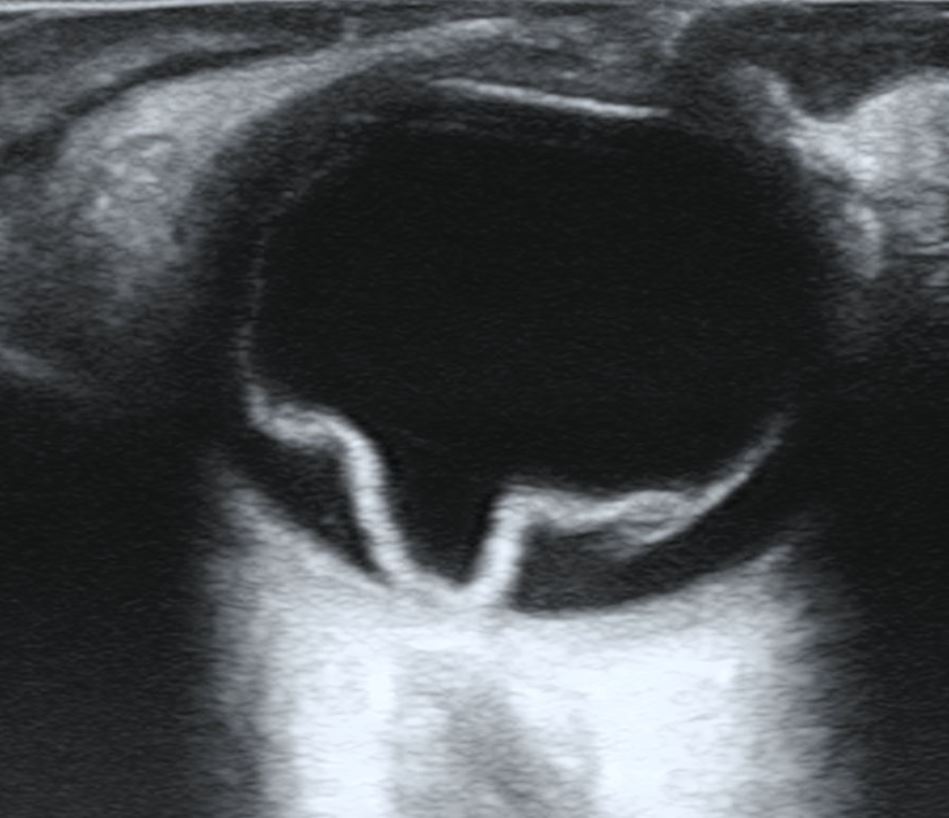

망막 박리를 보여주는 초음파 사진

망막의 시야가 불분명한 경우, 극광각 안저 사진 촬영, B-스캔 초음파 검사, 광학 단층 촬영법 (OCT)과 같은 영상 기술이 박리를 식별하는 데 도움이 될 수 있다.[4][13][14] 안저 사진 촬영은 눈 뒤쪽을 자세히 보여주며, 망막 열공 또는 파열을 나타낼 수 있다.[4][16] B-스캔 초음파 검사에서 박리된 망막은 일반적으로 유리체강에서 떠다니는 막으로 나타나며, 파동과 같은 움직임을 보인다.[19] OCT는 망막 뒤의 체액, 황반(망막의 중심 부분)의 침범, 망막층 내의 기타 이상을 감지할 수 있다.[4][20]

검사는 주로 안과에서 안저검사를 통해 망막 박리를 판정한다. 백내장이 심한 경우, 산동 곤란, 유리체 출혈 등으로 안저검사가 불가능한 경우에는 초음파 검사 장비를 사용하여 판정한다. CT나 MRI로 이차적으로 발견되기도 한다. 일반적으로 망막 박리 눈은 안압이 저하된다. 그러나 안압이 상승하고 전방 내 염증성 소견을 보이는 슈바르츠 증후군(Schwartz症候群)도 존재한다.